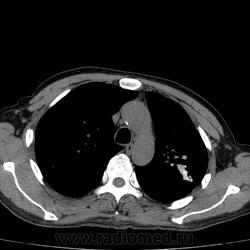

Рецидив туберкулеза?

Больной лечился по пневмонии. На КТ- контроле данные за рецидив туберкулеза (снят с учета в 10 году, асоциальный).

Нет, итл в/д левого л-го. Подняла архив, процесс был слева. Полость появилась справа, значит рецидив. Снят в прошл году с учета.

Придётся снова поставить на учёт.